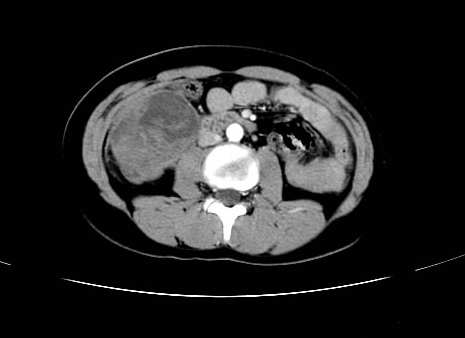

肿块最大径位于十二指肠降段与水平段移行处,并且与肝脏压迹呈“0”形征,可以考虑位于肝外并与胃肠道关系紧密,考虑胃肠道间质瘤(gist)可能较大,须除外神经节起源肿瘤。

肿块与十二指肠关系密切,支持间质瘤诊断.肝脏与结肠均为受压改变.

病灶巨大,少部分向肠腔内生长,大部分向长腔外生长。其密度不均匀,增强显示明显不均匀强化,并见有大片状始终不强化的不规则坏死液化区。虽然病灶中上部形态尚可,病人又如此年轻,但中下部形态、密度、强化特点强烈提示为恶性病灶。综上,我考虑本病例为:恶性胃肠道间质瘤。